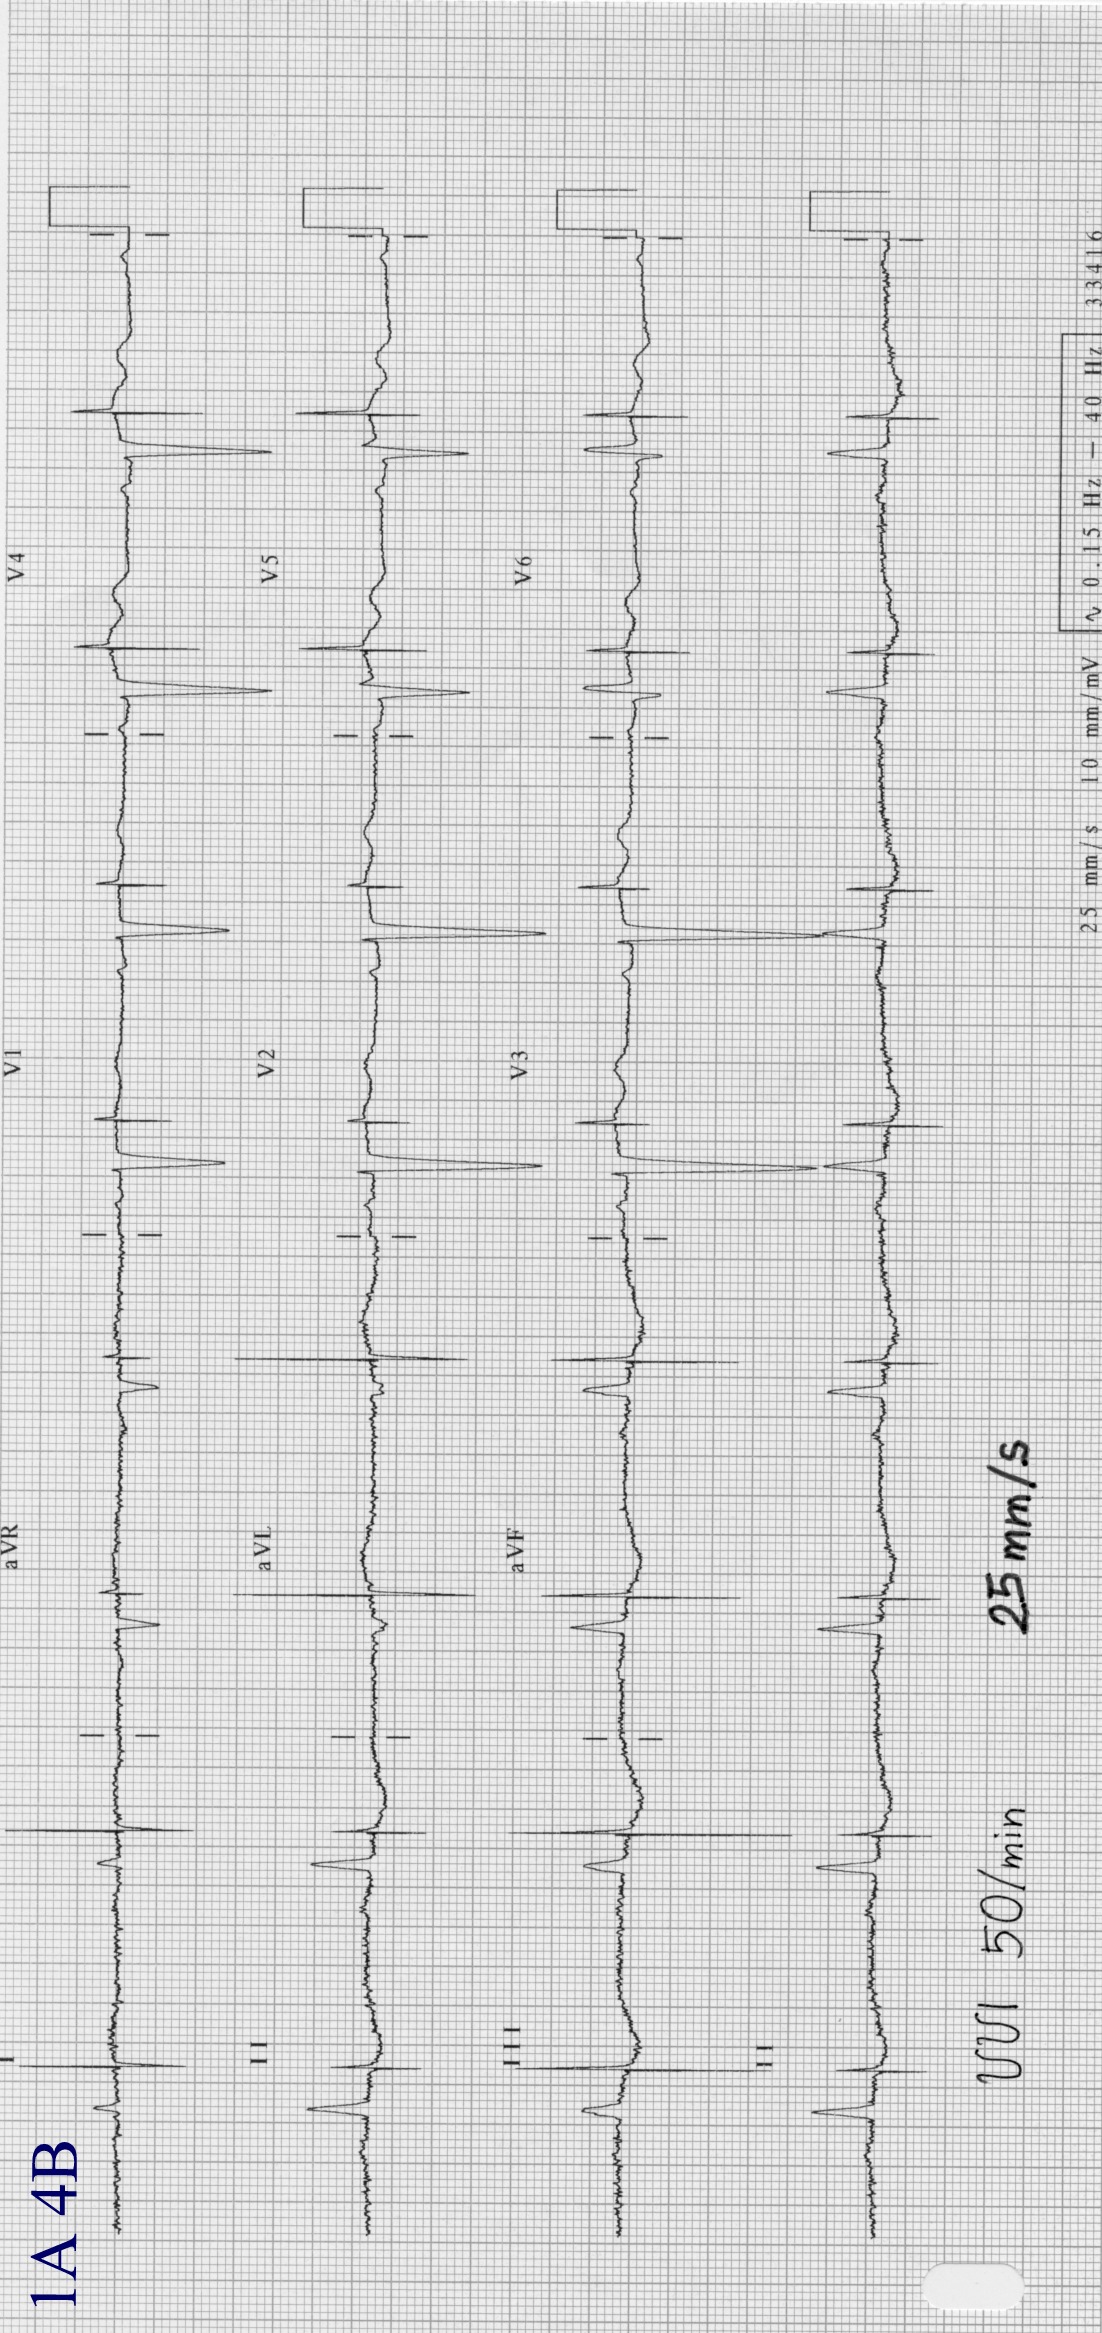

Zapis 1